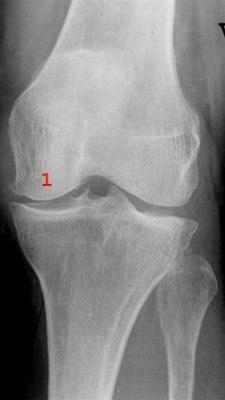

Røntgenbilde av kneleddetKneleddet utgjøres av lårbeinets og leggbeinets leddflater. Beinvevet er kledd med brusk som gjør at leddflatene glir mot hverandre med minst mulig motstand. I tillegg har kneleddet to bruskskiver (meniskene) som fremmer bevegeligheten i leddet. Artrose i kneleddet er den vanligste type revmatisk leddsykdom. Forandringer i leddbrusk og bein i leddet gjør at overflatene ikke lenger er glatte og symmetriske. Tidligere kaltes dette slitasjegikt. Begrepet er misvisende og brukes derfor ikke lenger.

Røntgen av kneet er vanligvis ikke nødvendig for å stille diagnosen. Hos personer som er 45 år eller eldre, har smerte i kneleddet som er relatert til fysisk aktivitet og ikke har morgenstivhet eller kun morgenstivhet med varighet opptil en halvtime, kan legen stille diagnosen uten å bestille tilleggsundersøkelser. Ved mistanke om andre underliggende årsaker kan det tas et røntgenbilde (stående), som kan bekrefte lette, moderate eller uttalte artroseforandringer.

Røntgenbildene forteller likevel ikke hele sannheten, fordi det kan være manglende samsvar mellom graden av plager og graden av forandringer på røntgen. Svært tidlige artroseforandringer kan ikke alltid påvises hos pasienter med begynnende plager. Motsatt kan pasienter med påviste røntgenforandringer ha beskjedne eller ingen symptomer. Tilleggsundersøkelser vil være nødvendig dersom symptombildet avviker fra det som forventes ved kneleddsartrose eller hvis pasienten henvises til vurdering av operasjon.